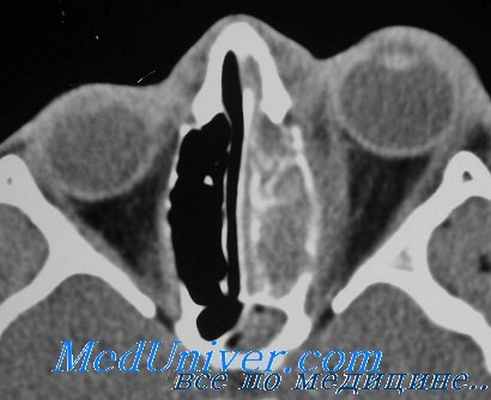

В нашей клинике, в рамках специализированной программы проводится лабораторная и инструментальная диагностика (гормональные и иммунологические анализы крови, УЗИ щитовидной железы, оценка орбитального статуса, экзофтальмометрия, периметрия, компьютерная томография орбит). При необходимости организуются консультации дополнительных специалистов. На основании результатов обследования офтальмологом и эндокринологом совместно определяется оптимальная тактика лечения.